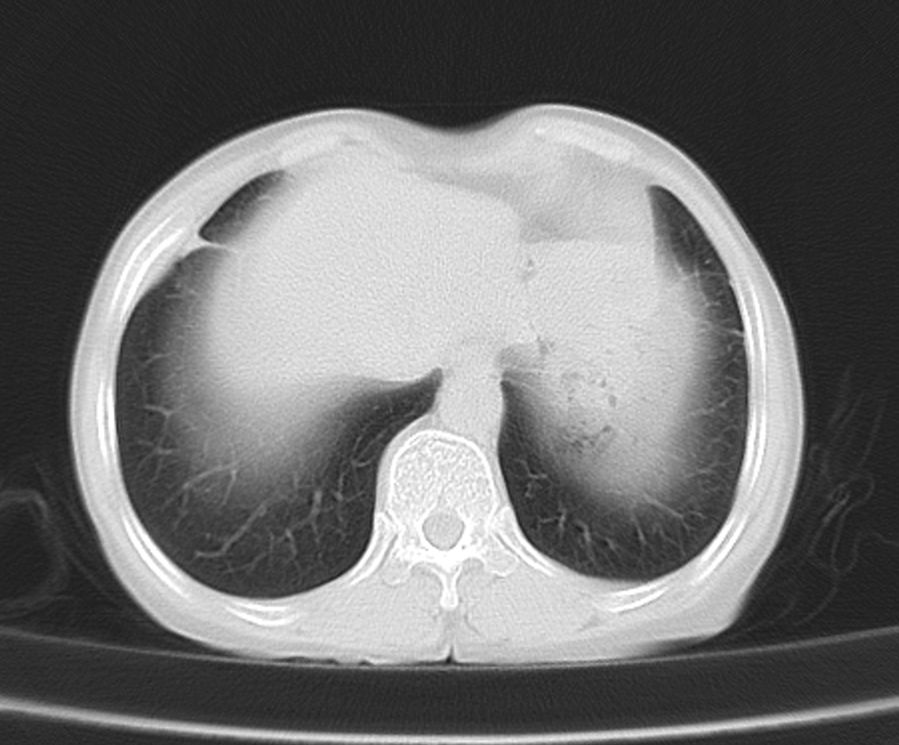

标题: CT21609:右乳包块1年,请各位讨论分析一下,乳腺CA, [打印本页]

标题: CT21609:右乳包块1年,请各位讨论分析一下,乳腺CA,

考虑---右乳癌并胸壁、肋骨、双肺转移。

考虑乳腺癌侵犯肋骨、胸壁及两肺转移可能性大。

右乳癌并胸壁、肋骨、双肺转移。

考虑右侧乳腺癌侵犯肋骨、胸壁及两肺转移。

支持考虑---右乳癌并胸壁、肋骨、双肺转移。

考虑右侧乳腺癌侵犯肋骨、胸壁及两肺转移可能。

考虑右侧乳癌并胸壁、肋骨及双肺多发性转移。

考虑右侧胸壁软组织肿瘤,肉瘤可能性大,双肺转移